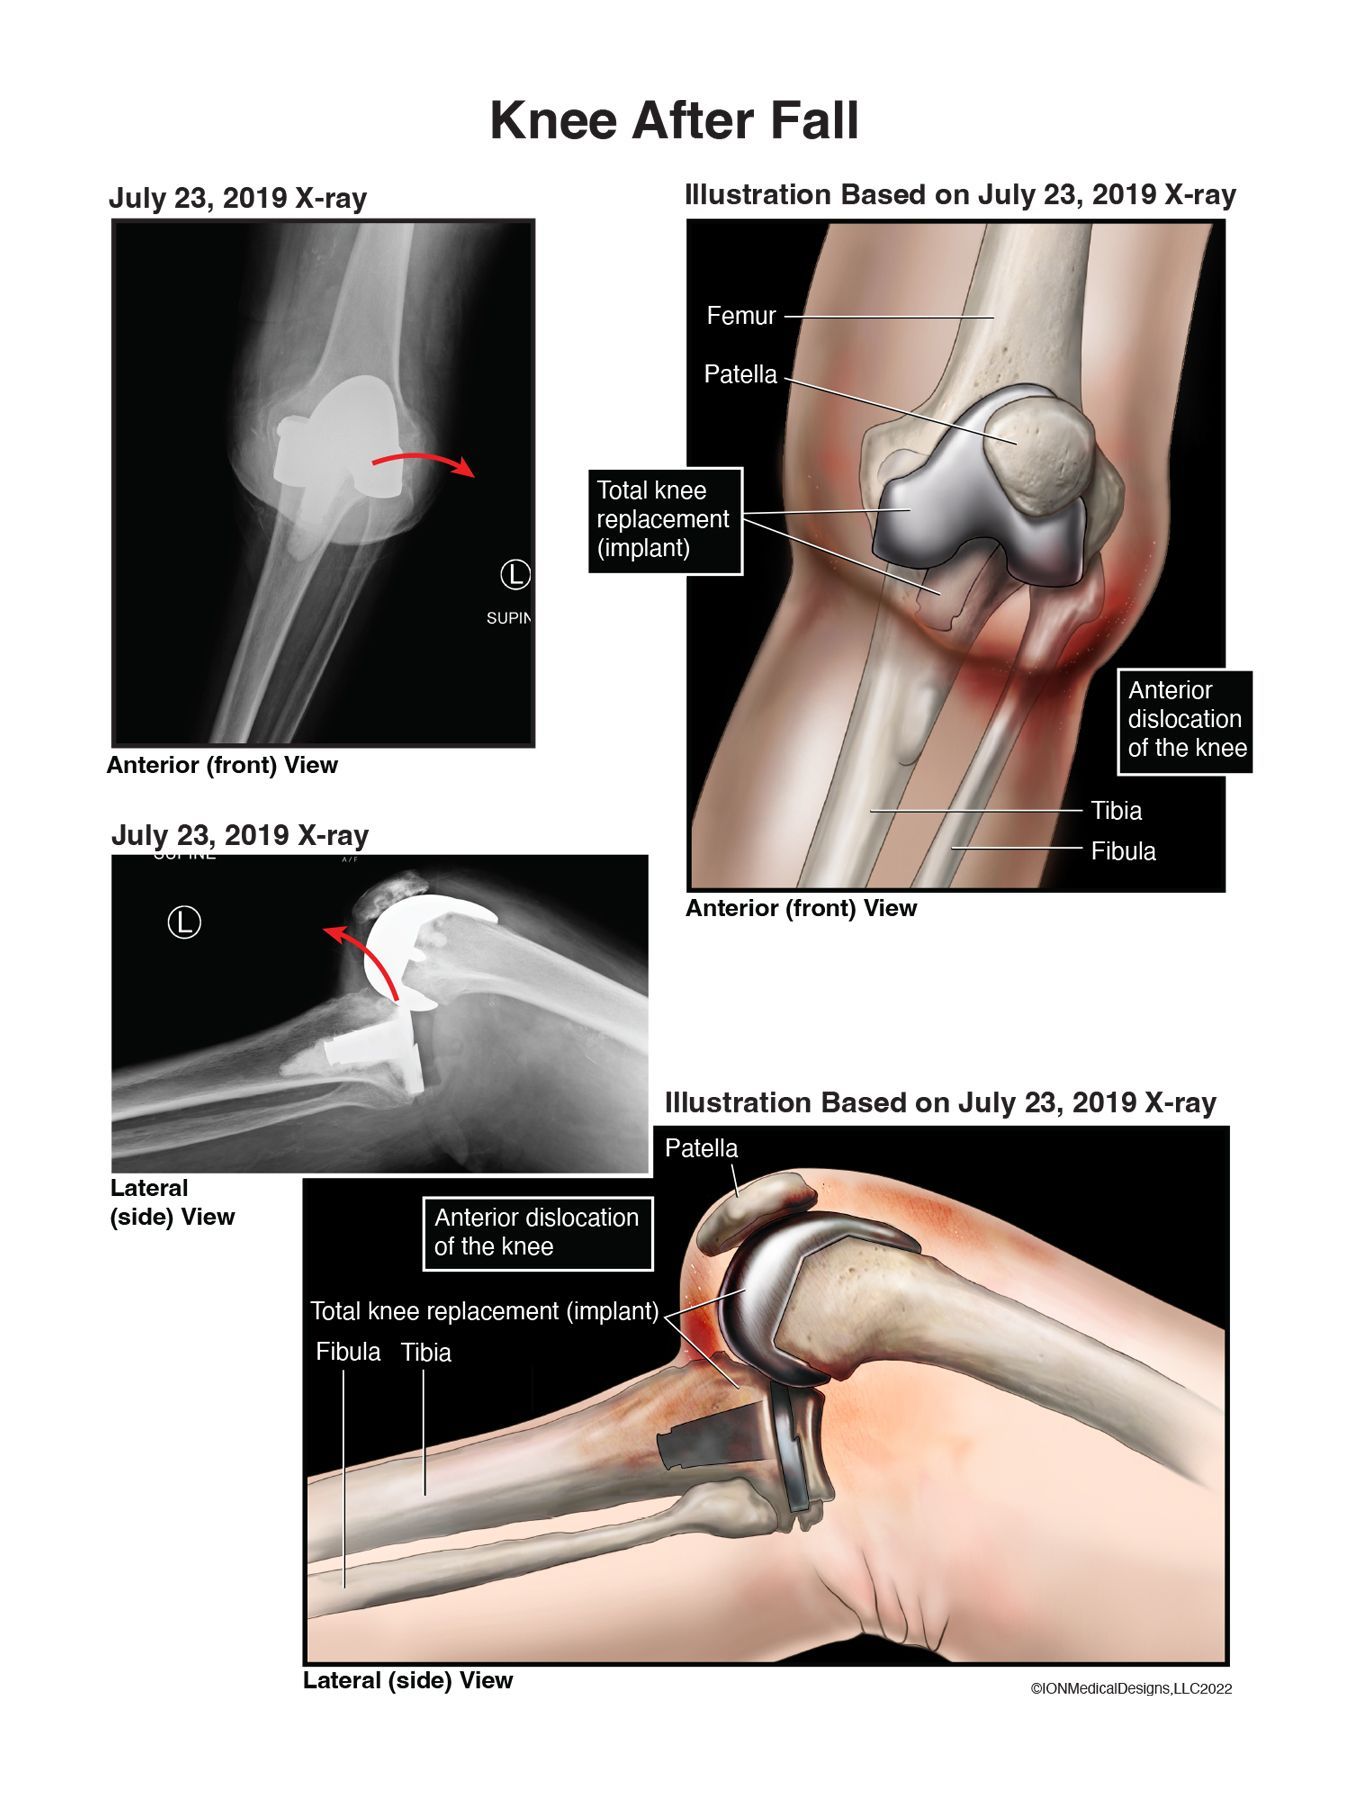

Knee After Fall

Fall after total knee replacement surgery resulting in a complete dislocation of the knee joint.